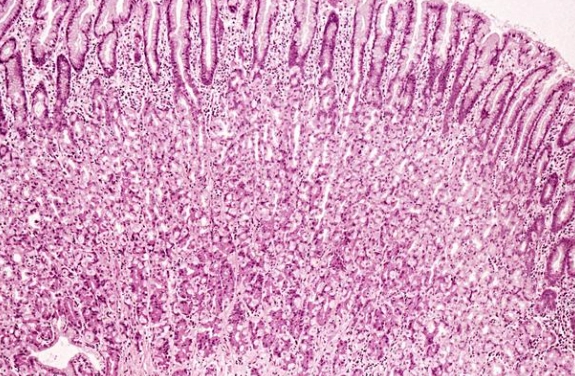

胃黏膜就是胃內壁的那層薄膜,厚度大約0.5到1.5毫米,別看它薄,功能可大了。它主要負責分泌胃酸和消化酶,幫助分解食物,同時保護胃壁不受胃酸侵蝕。你可以把它想像成胃的防護罩。

胃黏膜的結構與功能

胃黏膜分成好幾層,最表層是上皮細胞,它們會不斷更新。正常情況下,胃黏膜細胞每3到5天就會更新一次,這就是為什麼胃有自我修復能力。但如果你一直傷害它,修復速度就跟不上破壞速度。